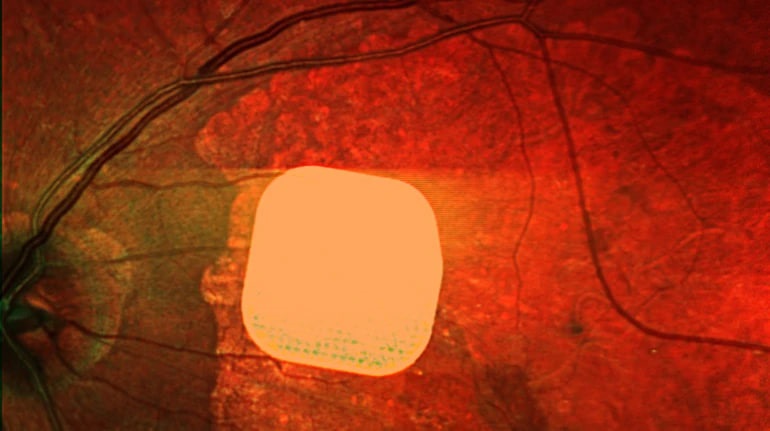

Британські лікарі здійснили важливий крок у боротьбі з віковою сліпотою, випробувавши новий електронний імплант Prima. Цей мікрочип, розміром лише 2×2 міліметри, допомагає частково відновити зір у пацієнтів із макулодистрофією, що є головною причиною втрати зору після 50 років. Під час операції пацієнту встановлюють цей чип під сітківку ока і під’єднують до системи окулярів з камерою і мінікомп’ютером. Камера перетворює зображення на інфрачервоний сигнал, який передається на мікрочип, що активує клітини сітківки, а потім сигнал доходить до мозку через зоровий нерв, утворюючи візуальне сприйняття. Дослідження показало, що після операції 84% пацієнтів знову змогли розрізняти літери, цифри та слова. Лікарі вважають, що ця технологія може значно покращити якість життя людей з важкими зоровими порушеннями, допомагаючи їм читати та бути більш незалежними.